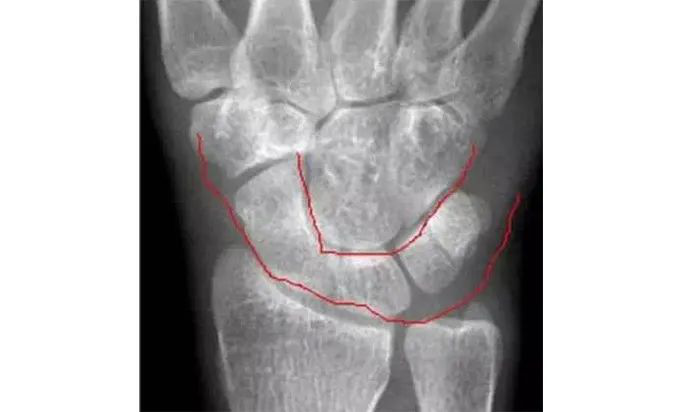

两条弧线如果不连通多半有脱位

若显示腕骨弧线不连续或各弧线不平行,或腕掌线M 形结构消失,应高度怀疑腕关节不稳或脱位。

Analyze - 腕骨弧线正位弧线不连续,侧位明显脱位。